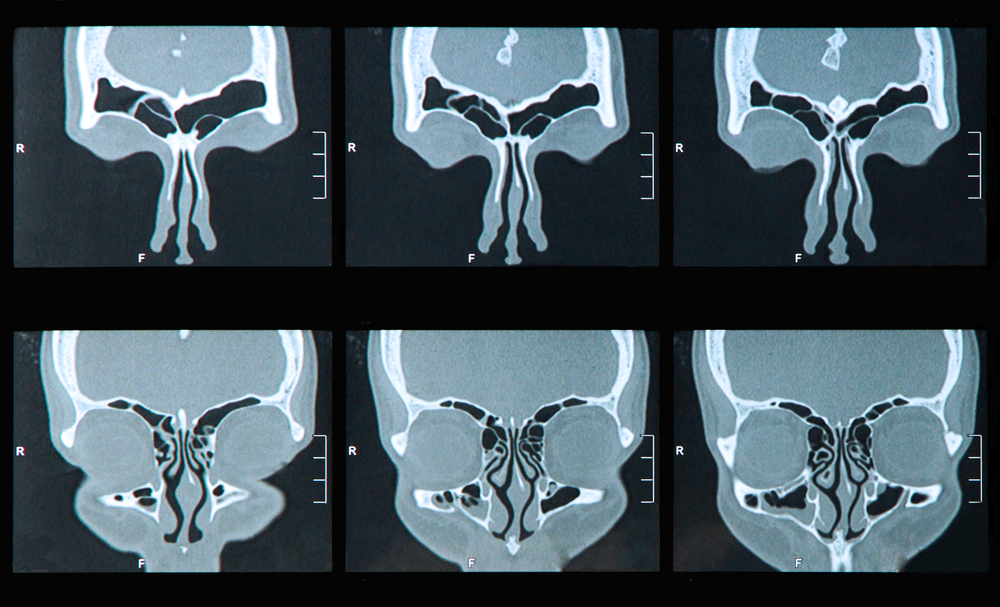

- рентгенография или КТ околоносовых пазух;